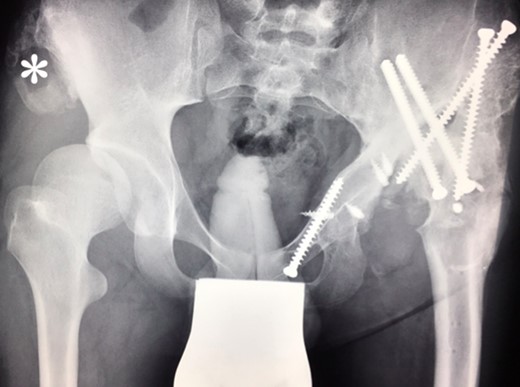

(2009) Despite conservative treatment the right hip subluxates. There is new bone formation at the proximal os ileum (asterisk) without trauma. The acetabulum is still congruent and decision was made to restore the hip joint by surgery.

At this stage patient’s walking ability was already limited due to muscle weakness and rubbing in the hip joints, so we recommended no further walking and weight bearing. Further follow-up at 5 years (Fig. 7) and 10 years (Fig. 8A) until today showed radiologically complete absorption of the left femoral head and the right hip continuously moving cranially creating a false acetabulum and a flattened femoral head. At final follow up the patient was in a wheel chair but able to bend both hips up to 110 degrees without noticeable pain, he could stand up with help for a short time and showed a massive Charcot joint with effusion (Fig. 8B) of the right hip without further clinical implications.